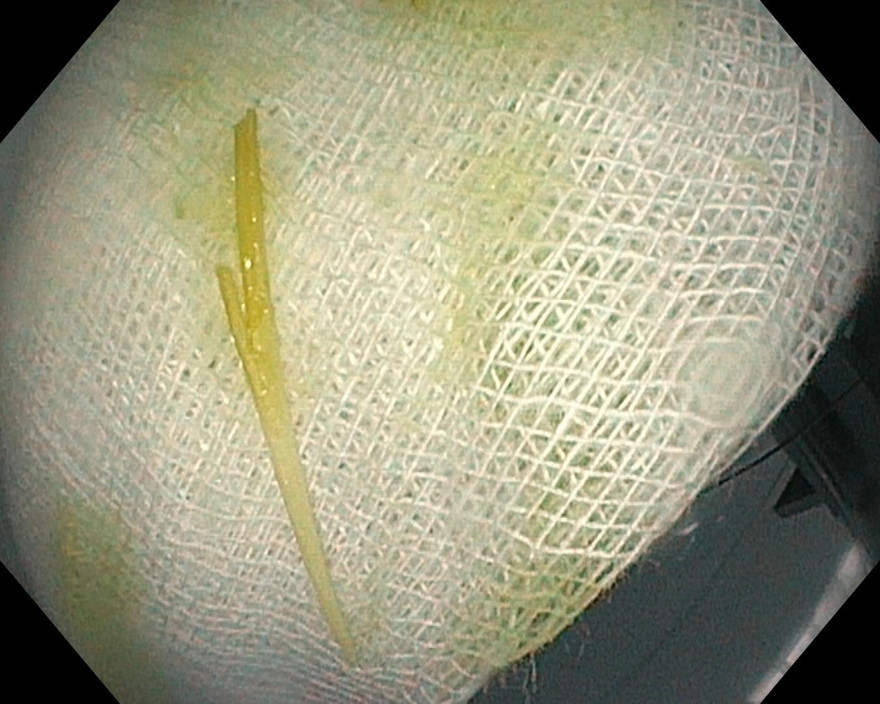

Khi nội soi đến đoạn D3 tá tràng, các bác sĩ phát hiện dị vật đó là một que tăm xỉa răng, một đầu tăm đã đâm xuyên thành tá tràng. Ngay sau đó que tăm đã được gắp ra hoàn toàn. Vị trí thành ruột bị tăm đâm không chảy máu, có lỗ thủng rất nhỏ.

Dị vật ghi nhận trong lúc nội soi.